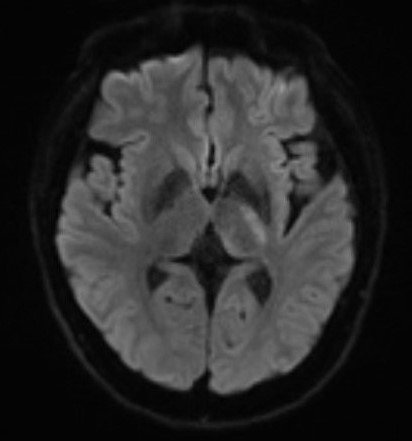

Case Summary: In less than 400 words, please summarize the case. Briefly describe the case and any particular complexities and/or complications encountered.: A 43-year-old man was diagnosed with Fabry disease when he had lacunar infarction of right putamen 8 years before the admission and was treated with agalsidase α. He had recurrent infarction in the right side of the midbrain 6 years ago and in the left corona radiata last year, but was independent in daily life with only residual right lower extremity sensory disturbance and modified Rankin Scale score was 1. This time, he was presented to our hospital with sudden-onset right hemiplegia and dysarthria from the time he woke up, and his NIHSS score was 2. Head MRI showed acute cerebral infarct in the left internal capsula. He was hospitalized and dual antiplatelet therapy (cilostazol 200 mg added to the aspirin 100 mg that he had been taking) initiated as acute lacunar infarction, but a few hours later, his right hemiplegia worsened in stepwise, and he also developed sensory deficit in the right side of his body. On the same night, his NIHSS score worsened to 5 and argatroban infusion was added, but his right hemiplegia continued to worsen. On the second day, his NIHSS score reached 10, and he required tube feeding due to marked dysphagia caused by pseudobulbar palsy. Follow-up head MRI performed on the 12th day showed that the infarct was enlarged in the anterior-posterior direction, and the course of disease was compatible with branch atheromatous disease (BAD). After rehabilitation, his right hemiplegia and pseudobulbar palsy improved with time, and he was weaned off tube feeding. He was transferred to a rehabilitation hospital on his 53rd day with a NIHSS score of 3 and mRS score of 4.